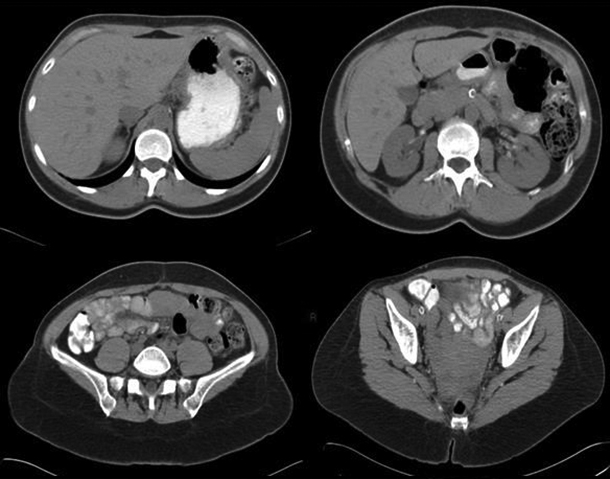

Fig. 6. TC preoperatoria.

Caso 2

Paciente de sexo masculino de 40 años de edad, diabético tipo 1, sin hemodiálisis. Presentó una tomografía preoperatoria sin calcificaciones en la pared del sistema vascular (Fig. 6). El paciente manifestó dolor abdominal y presentó fiebre posterior al acto quirúrgico, lo cual determinó la realización de una TCMD con contraste EV (Fig. 7). Los niveles de laboratorio post operatorio de glucemia, lipasa y amilasa fueron: 148mg/dl, 37 U/L y 150 U/L, respectivamente.